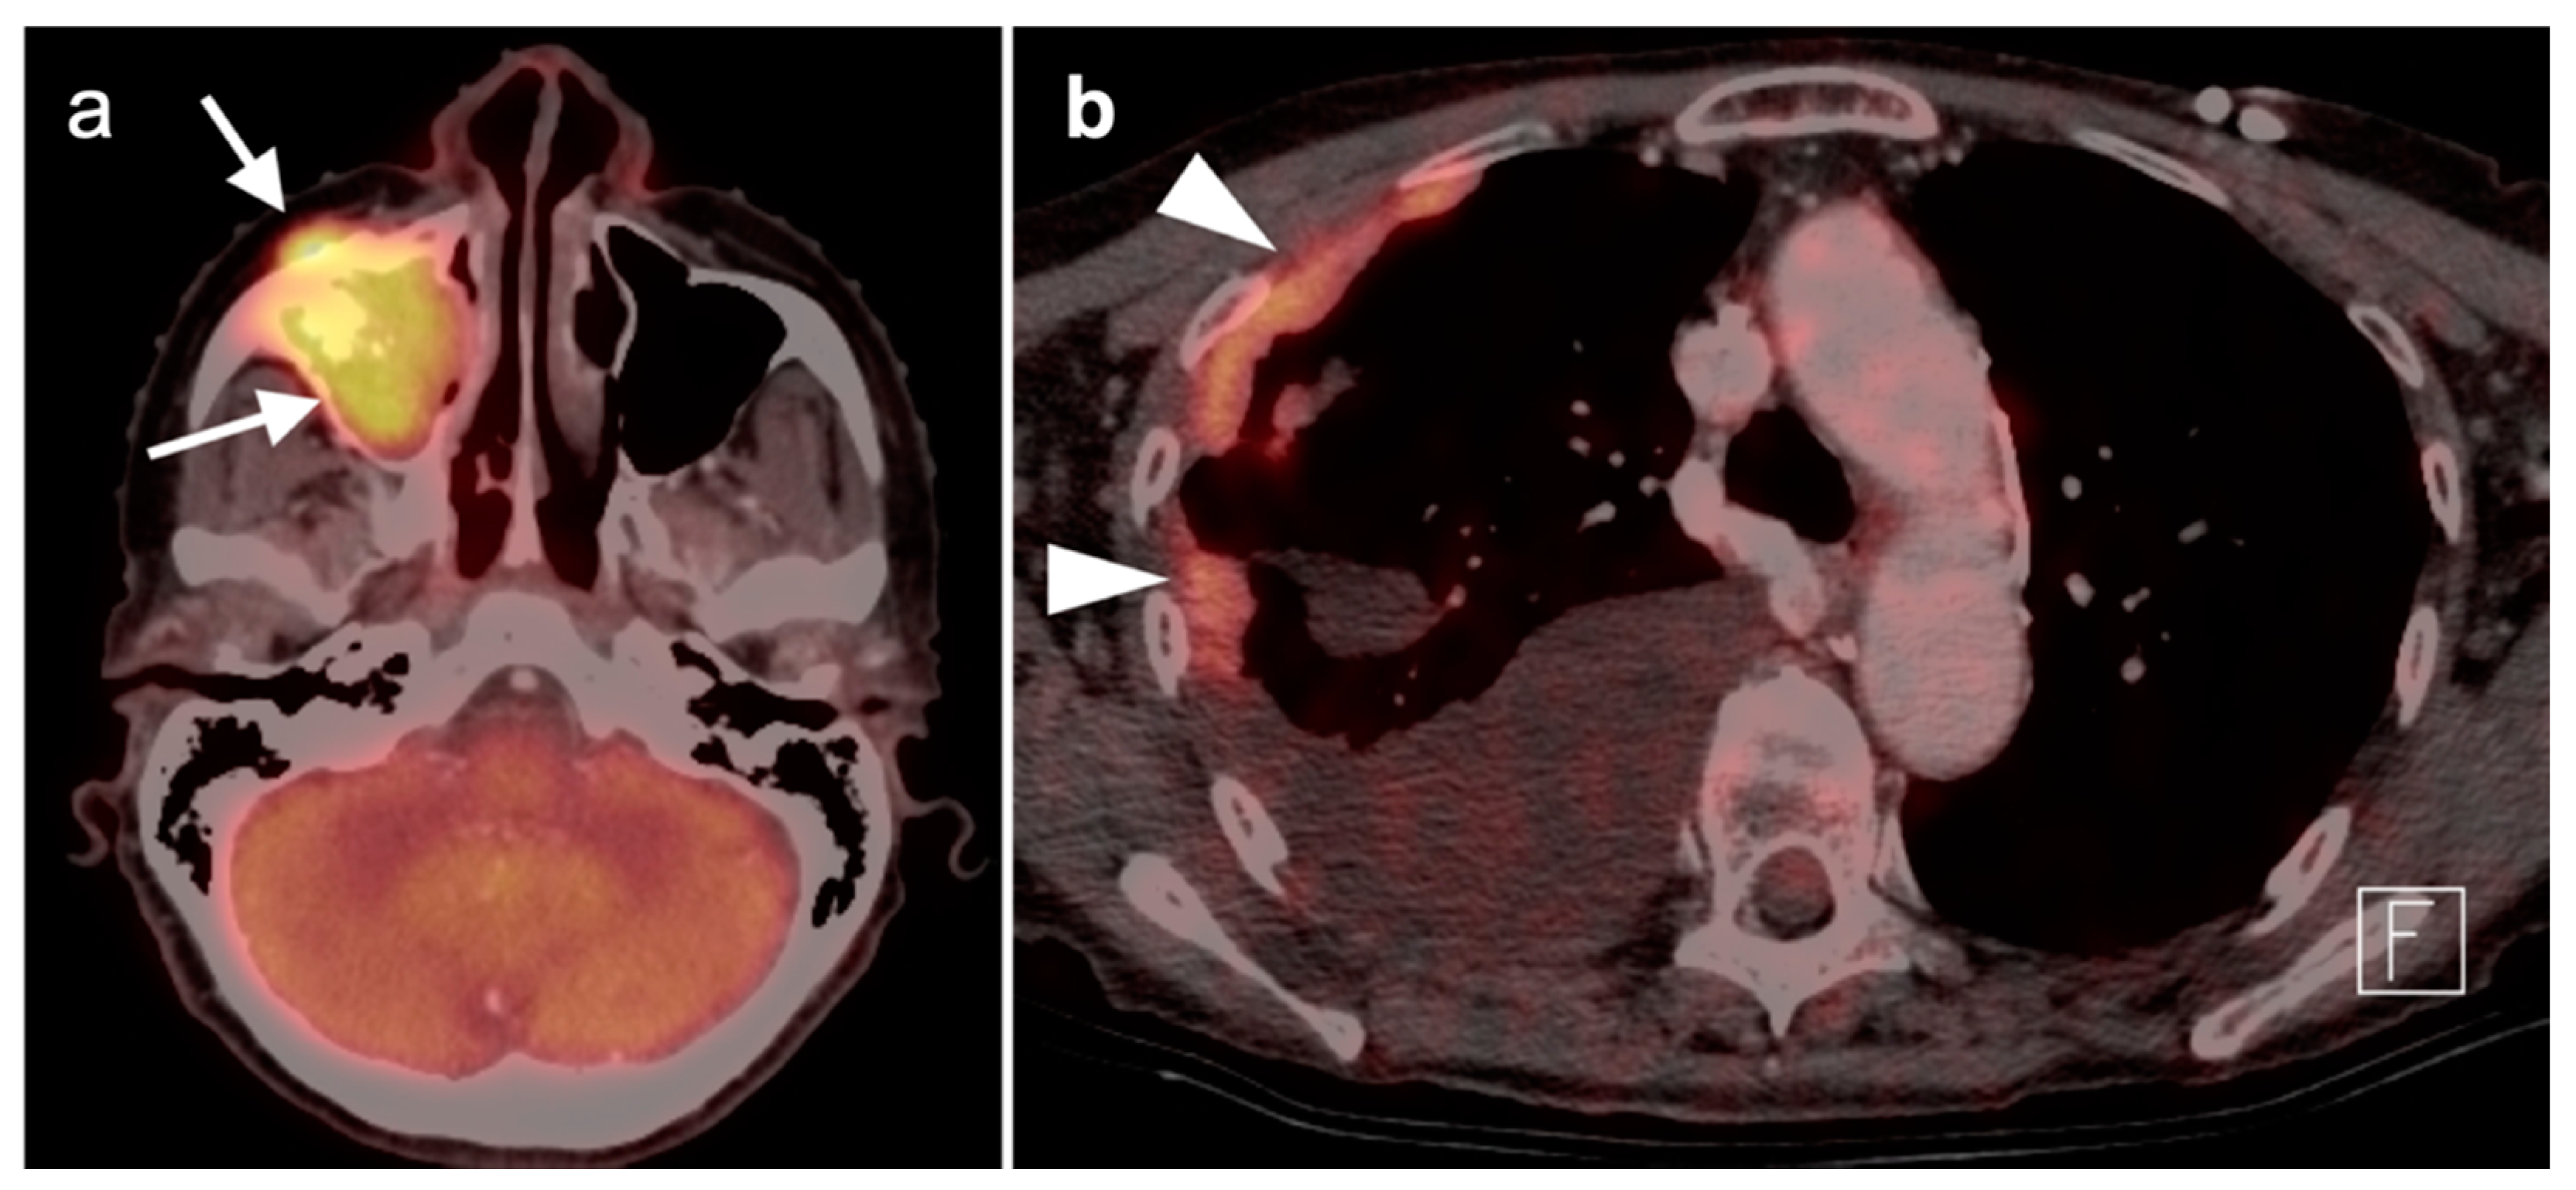

2.4. Sinonasal Tumors

- Eggesbø, H.B. Imaging of sinonasal tumours. Cancer Imaging 2012, 12, 136–152. [Google Scholar] [CrossRef] [PubMed]

- Kawaguchi, M.; Kato, H.; Tomita, H.; Mizuta, K.; Aoki, M.; Hara, A.; Matsuo, M. Imaging Characteristics of Malignant Sinonasal Tumors. J. Clin. Med. 2017, 6, 116. [Google Scholar] [CrossRef] [PubMed]

- Ozturk, K.; Gencturk, M.; Caicedo-Granados, E.; Li, F.; Cayci, Z. Utility of FDG PET/CT in the Characterization of Sinonasal Neoplasms: Analysis of Standardized Uptake Value Parameters. AJR Am. J. Roentgenol. 2018, 211, 1354–1360. [Google Scholar] [CrossRef] [PubMed]

- Ozturk, K.; Gencturk, M.; Rischall, M.; Caicedo-Granados, E.; Li, F.; Cayci, Z. Role of Whole-Body 18F-FDG PET/CT in Screening for Metastases in Newly Diagnosed Sinonasal Malignancies. AJR Am. J. Roentgenol. 2019, 212, 1327–1334. [Google Scholar] [CrossRef]

- Maurer, A.; Meerwein, C.M.; Soyka, M.B.; Grünig, H.; Skawran, S.; Mühlematter, U.J.; Messerli, M.; Mader, C.E.; Husmann, L.; Rupp, N.J.; et al. Whole-body hybrid positron emission tomography imaging yields clinically relevant information in the staging and restaging of sinonasal tumors. Head Neck 2021, 43, 3572–3585. [Google Scholar] [CrossRef]